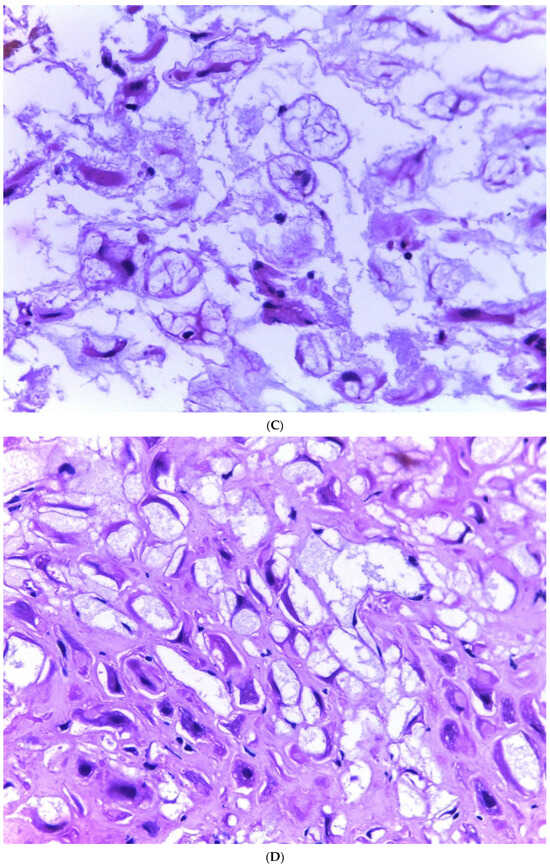

A total of 776 cases of endometriosis were collected between the two institutions that participated in the study, in different anatomical sites (Table 1, Scheme 1), of which 54 presented with a myxoid stroma >50% with respect to the cellularity of the samples and represented 6.95% of the total endometriosis examined, with the following locations: omentum (4/20), ileum (2/4), ovary (14/216), parametria (2/9), soft tissues (28/235), salpingus (3/77), and bladder (1/4). The clinical records of these patients were consulted, and the common denominator was that these women were in the surgical (41/57) or physiological (7/39) puerperium during 24 h postpartum to 6 months after said event. Macroscopically, two different lesions were observed: the first one, which is the most frequent, presents as a non-encapsulated lesion with pushing edges of a fibromyxoid appearance; the second and less frequent, is a well-defined lesion, partially or totally encapsulated, with a shiny cut surface, gelatinous in appearance, multilobed, and light brown to brown in color with focal areas of recent and old hemorrhage; these lobes are separated by fibrous septa (Figure 1). Histologically, it was found that in all the samples evaluated, at least 50% of myxoid stroma with some fine connective tissue septa with the proliferation of stromal cells (Figure 2A) presented the following four variants in their shape: (1) Epithelioid stromal cells of wide eosinophilic cytoplasm with round small nuclei (Figure 2B), (2) pseudolipoblast-type stromal cells with moderate cytoplasm, multivacuolated in their cytoplasm that can present eosinophils or clear cytoplasm, with central nuclei of granular chromatin (Figure 2C), (3) “pseudosignet ring” stromal cells with the nucleus and cytoplasm rejected to the periphery giving the described appearance (Figure 2D), and (4) immersed spindle cells with discrete nuclei (Figure 2E). Among these cells, the epithelial component was observed, with tubules ranging from small to large cystic dilations of the gland that present a layer of low cubic to cylindrical epithelium, generally with an atrophic appearance (Figure 2F). Hyaline globules were found in the glandular lumens (Figure 2G). The extracellular matrix showed a composition of glycosaminoglycans in 100% of the cases by staining present for AA (Figure 3A–C), but without staining for PAS; however, the latter stained on proteinaceous globular material in the lumen of the endometrial glands (Figure 3D). Immunohistochemistry for CD10 was positive in 100% of the stromal cells with a mild to moderate reaction in the cytoplasm and membrane with a decidual appearance (Figure 4A,B). The ER and PR showed nuclear expressions in 100% of cases, with greater intensity in the ER (Figure 4C) than PR (Figure 4D); both hormone receptors were expressed on the endometrial epithelial and stromal cells. The cases of myxoid endometriosis examined did not present cytological atypia, suggesting any precursor lesion of epithelial or stromal origin.

Figure 2.

Histologic features of myxoid endometriosis. (A) Myxoid stroma in ≥50% of the tissue, with proliferation of stromal cells. Identified stromal cell variants: (B) epithelioid cells, (C) lipoblast-like cells, (D) signet-ring-like cells, and (E) spindle cells. (F,G) Epithelial components formed by glands of variable size, with simple cuboidal to columnar epithelium with a non-atypical atrophic appearance occasionally accompanied by luminal hyaline globules.